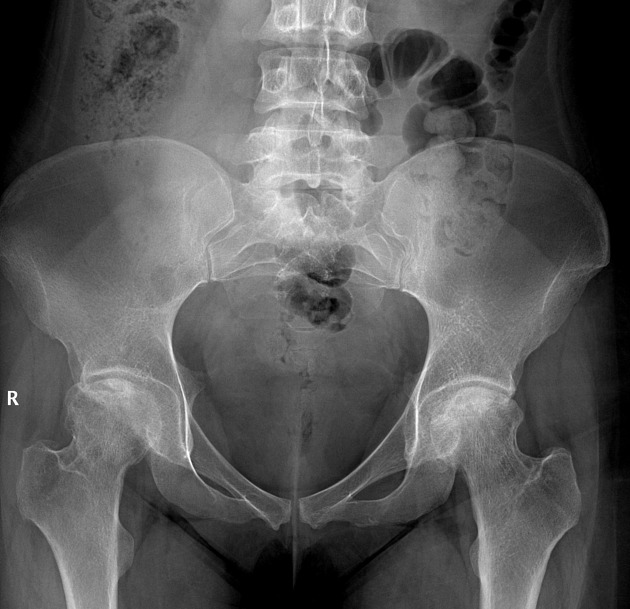

Düz Röntgen (Erken Evre X-Ray) Sens. %15 - 25 Spe. %90+ LR+ 1.5 LR- 0.85

Erken evrede negatif çıkması hastalığı ekarte ettirmez (körlüktür). Sadece geç evre çöküşü gösterir.

3. Radyolojik Evreleme ve "Geri Dönüşü Olmayan Nokta" Analizi

Görüntüleme bir fotoğraf değil, bir zaman çizelgesidir. Amacımız subkondral çökmenin (Point of No Return) ne zaman gerçekleşeceğini öngörmektir.

Evre 0: Röntgen ve MR normal. Semptom yok / Şüphe. (LR+ = 1.0)

Evre I: Röntgen normal, MR pozitif (Çift Çizgi). Hafif ağrı. (LR+ 15.0 - Tanı kesin)

Evre II: Skleroz, kistik değişiklikler. Belirgin ağrı. (LR+ 10.0 - Röntgen tanısaldır)

Evre III: Crescent Sign (Hilal Belirtisi). Şiddetli ağrı, subkondral kırık ve çökme başlar. (LR+ - ∞ - Biyomekanik iflas)

Evre IV: Eklem aralığında daralma, ileri osteoartrit. Terminal safha.